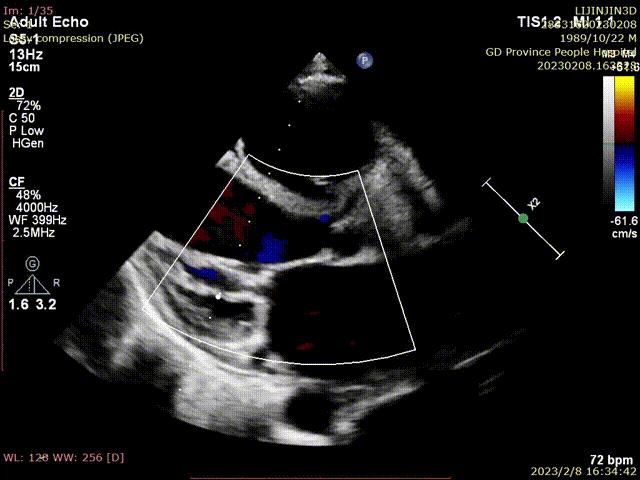

术后超声,零反流

出院前,几乎零反流。

患者返流宽度不大,一个短宽夹子可以完成,操作上没有太大挑战。术前左房压超过50mmHg,术后即刻降低到25mmHg以下,术后复查心脏彩超,左室缩小,EF值明显改善,期待随访的效果。